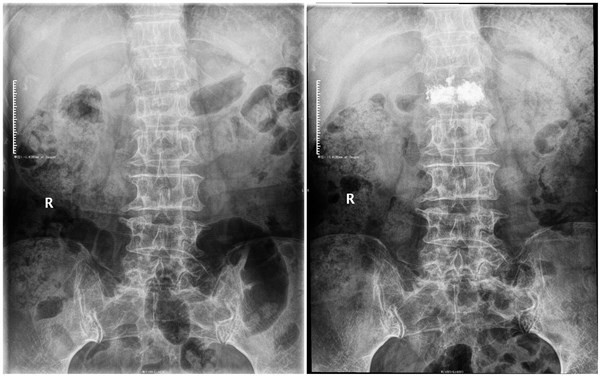

腰1椎体压缩性骨折术前术后正位片

腰1椎体压缩性骨折术前术后侧位片